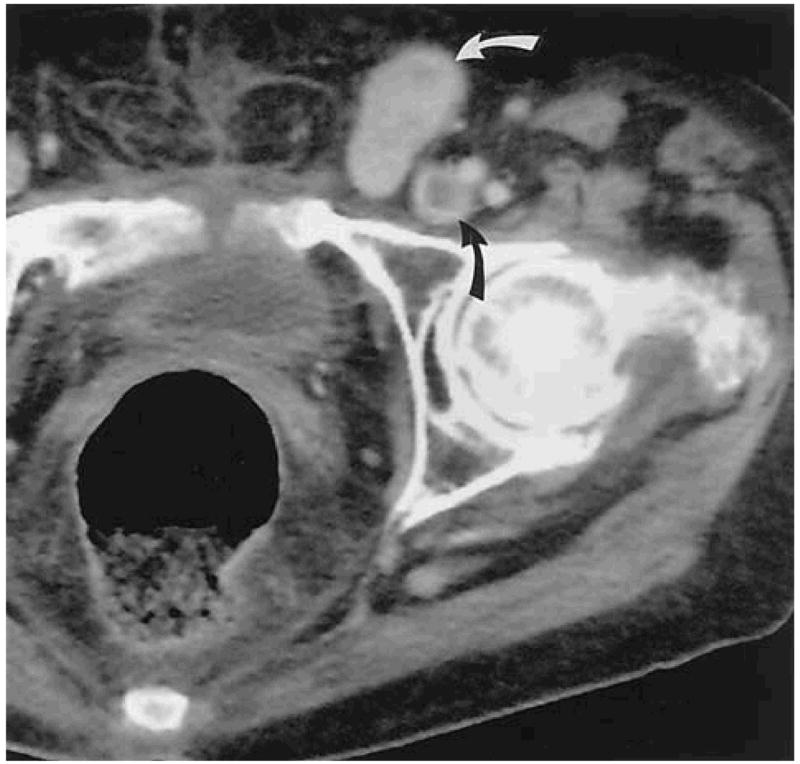

Bệnh nhân nữ, 58 tuổi, tiền sử ung thư ống vòi trứng> 2 năm.

A. Khối di căn phần mềm vùng bẹn trái, kèm huyết khối tĩnh mạch đùi (mũi tên đen), khối ngấm thuốc mạnh sau tiêm (mũi tên trắng).

B. Khối phần mềm sau khi đốt sóng cao tần không còn ngấm thuốc sau tiêm.